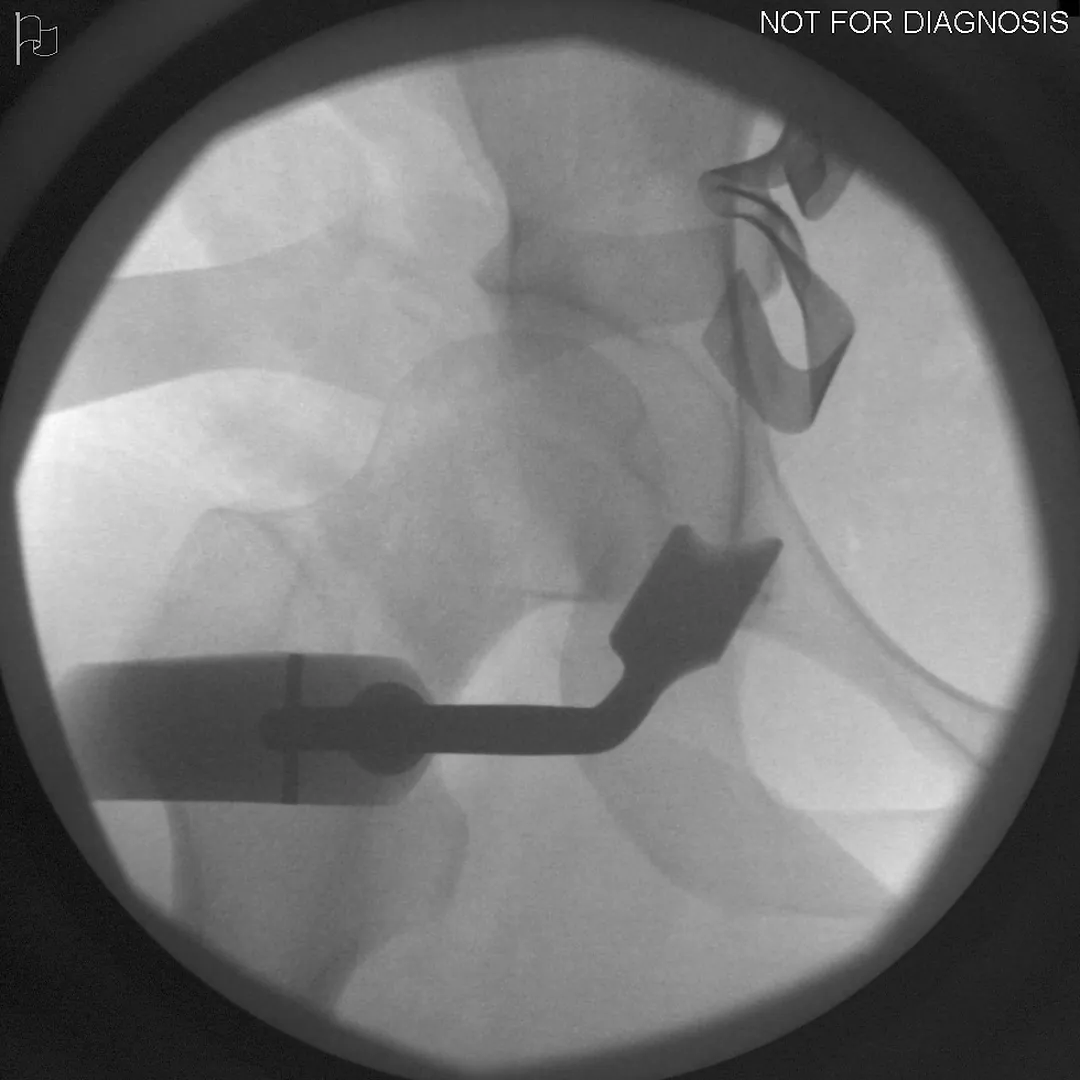

During a PAO, the surgeon carefully cuts the bone around the hip socket and repositions it to provide better coverage of the femoral head. The socket is then fixed in its new position using screws. The goal is to improve hip stability, reduce pain, and preserve the patient’s natural hip joint.

• Screws shown securing the acetabulum in its new position

• Several controlled bone cuts are made around the hip socket

• The socket is repositioned and fixed with screws

• The hip joint itself is preserved

Screw Removal

In most cases, the screws are left in place. However, if they cause irritation, removal can be considered after the bone has healed, which is typically 9-12 months after the initial PAO.